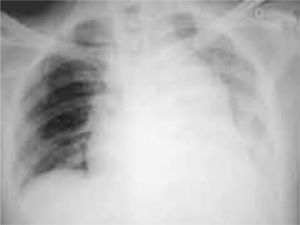

Realizamos el procedimiento a través de esternotomía media (Fig. 4); la aorta se observa en posición normal con una proporción de diámetro inversa respecto al tronco de la pulmonar, ya que prácticamente su diámetro es un 50% más pequeño; el arco aórtico se encuentra a la izquierda y las arterias coronarias a simple vista se perciben muy dilatadas y tortuosas pero con un trayecto normal. La arteria anómala se origina del seno de Valsalva izquierdo del tronco pulmonar, lográndose identificar desde su origen aparente en la parte posterolateral izquierda del tronco de la arteria pulmonar a 1,5cm de distancia de la unión ventriculoarterial. El tronco de la arteria pulmonar se observó dilatado (5,5cm), palpándose además un frémito correspondiente a la fístula ocasionada por el drenaje anómalo de la circulación coronaria izquierda hacia el tronco pulmonar. Se decidió realizar la ligadura del tronco de la arteria coronaria izquierda en el origen de la arteria pulmonar, así como la revascularización miocárdica de la arteria descendente anterior con injerto pediculado de arteria mamaria interna izquierda por el tamaño de la arteria pulmonar, que dificultaba la disección. Fue dado de alta después de un postoperatorio sin complicaciones. Un año después, el paciente se mantiene asintomático y con disminución radiográfica considerable del arco que representa a la arteria pulmonar (Fig. 5). Por otro lado, se ha reintegrado a sus actividades y sólo se mantiene en vigilancia médica.